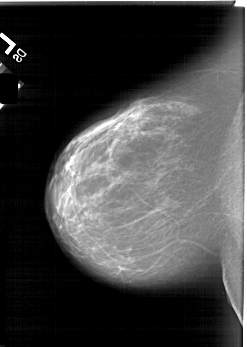

A_1813_1.LEFT_CC

LEFT_CC LINES 6241 PIXELS_PER_LINE 4441 BITS_PER_PIXEL 12 RESOLUTION 43.5 NON_OVERLAY